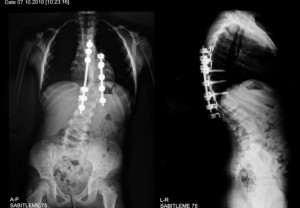

June is National Scoliosis Awareness Month so we have included topics discussing spinal stenosis, ankylosing spondylitis, low back pain, and spinal muscular strophy. Scoliosis is a curvature in the spine which typically can occur during puberty. Common treatment for scoliosis is wearing a brace for several hours throughout the day but if the curvature is greater than 45 degrees than surgery may be required.

Scoliosis in adults is an abnormal spine curvature, also known as degenerative scoliosis. Degenerative scoliosis is the gradual deterioration of the facet joints, similarly seen in osteoarthritis of the spine. The main difference between degenerative scoliosis and osteoarthritis of the spine is that pressure from the deteriorating facet joints in degenerative scoliosis causes the spine to curve off to one side.

There are two main categories of adult scoliosis: adult idiopathic scoliosis and adult “De Novo” or degenerative scoliosis. In adult idiopathic scoliosis, the patient developed scoliosis as a child or adolescent, but because there is no known cause for scoliosis, it is idiopathic. “De Novo” or degenerative scoliosis is the degeneration of the facet joints, where a person can lose height as the spine curves to one side.